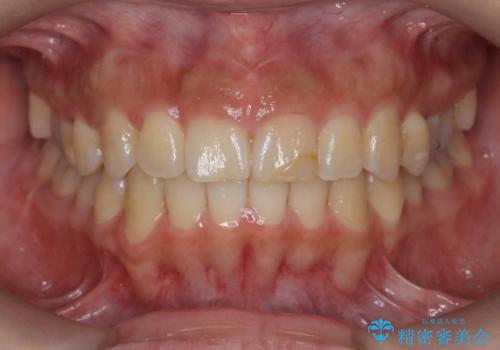

30代女性 前歯のがたつき